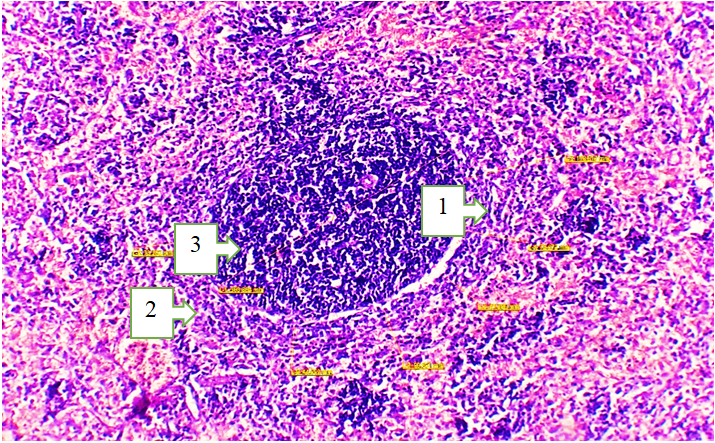

The spleens of 18-month-old healthy non-pedigreed rats were examined, and the following data were obtained:The body weight of 18-month-old animals ranged from 290 g to 320 g, with a mean of 312.26 ± 3.68 g. The absolute spleen weight ranged from 1.3 g to 1.7 g, with a mean of 1.52 ± 0.037 g. The spleen weight index varied between 0.333% and 0.552%, averaging 0.455 ± 0.024%.The spleen length ranged from 29.4 mm to 35.2 mm, with an average of 33.78 ± 0.63 mm, showing a growth rate of −22.0%. The spleen width ranged from 4.6 mm to 7.4 mm, averaging 6.52 ± 0.26 mm. The spleen thickness ranged from 2.8 mm to 3.9 mm, with a mean of 2.92 ± 0.29 mm, showing a growth rate of 243.3%. | Picture 1. Morphological structure of the spleen tissue of an 18-month-old white outbred rat. Staining: H&E. Obj. 4x20, ocular 2x. 1. Atrophic changes in the red pulp, increased hemolysis in the perisinusoidal area. 2. The white pulp area is reduced in size: the number of mature cells in the lymphoid follicles has decreased, while the number of blast cells has increased. 3. The mantle and marginal zones are reduced |